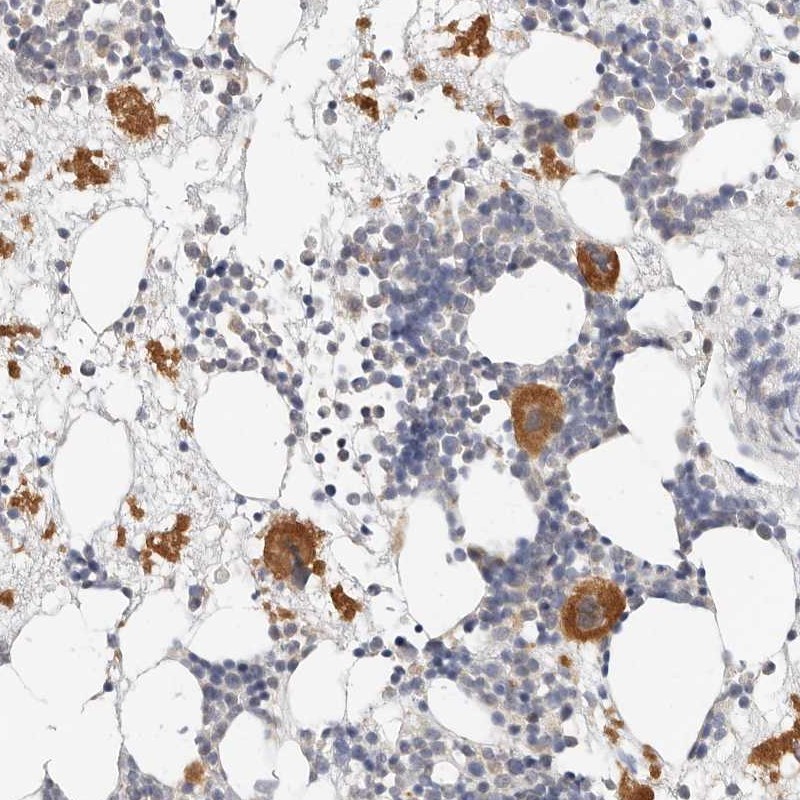

Immunohistochemical staining of human bone marrow shows distinct cytoplasmic positivity in bone marrow poietic cells.